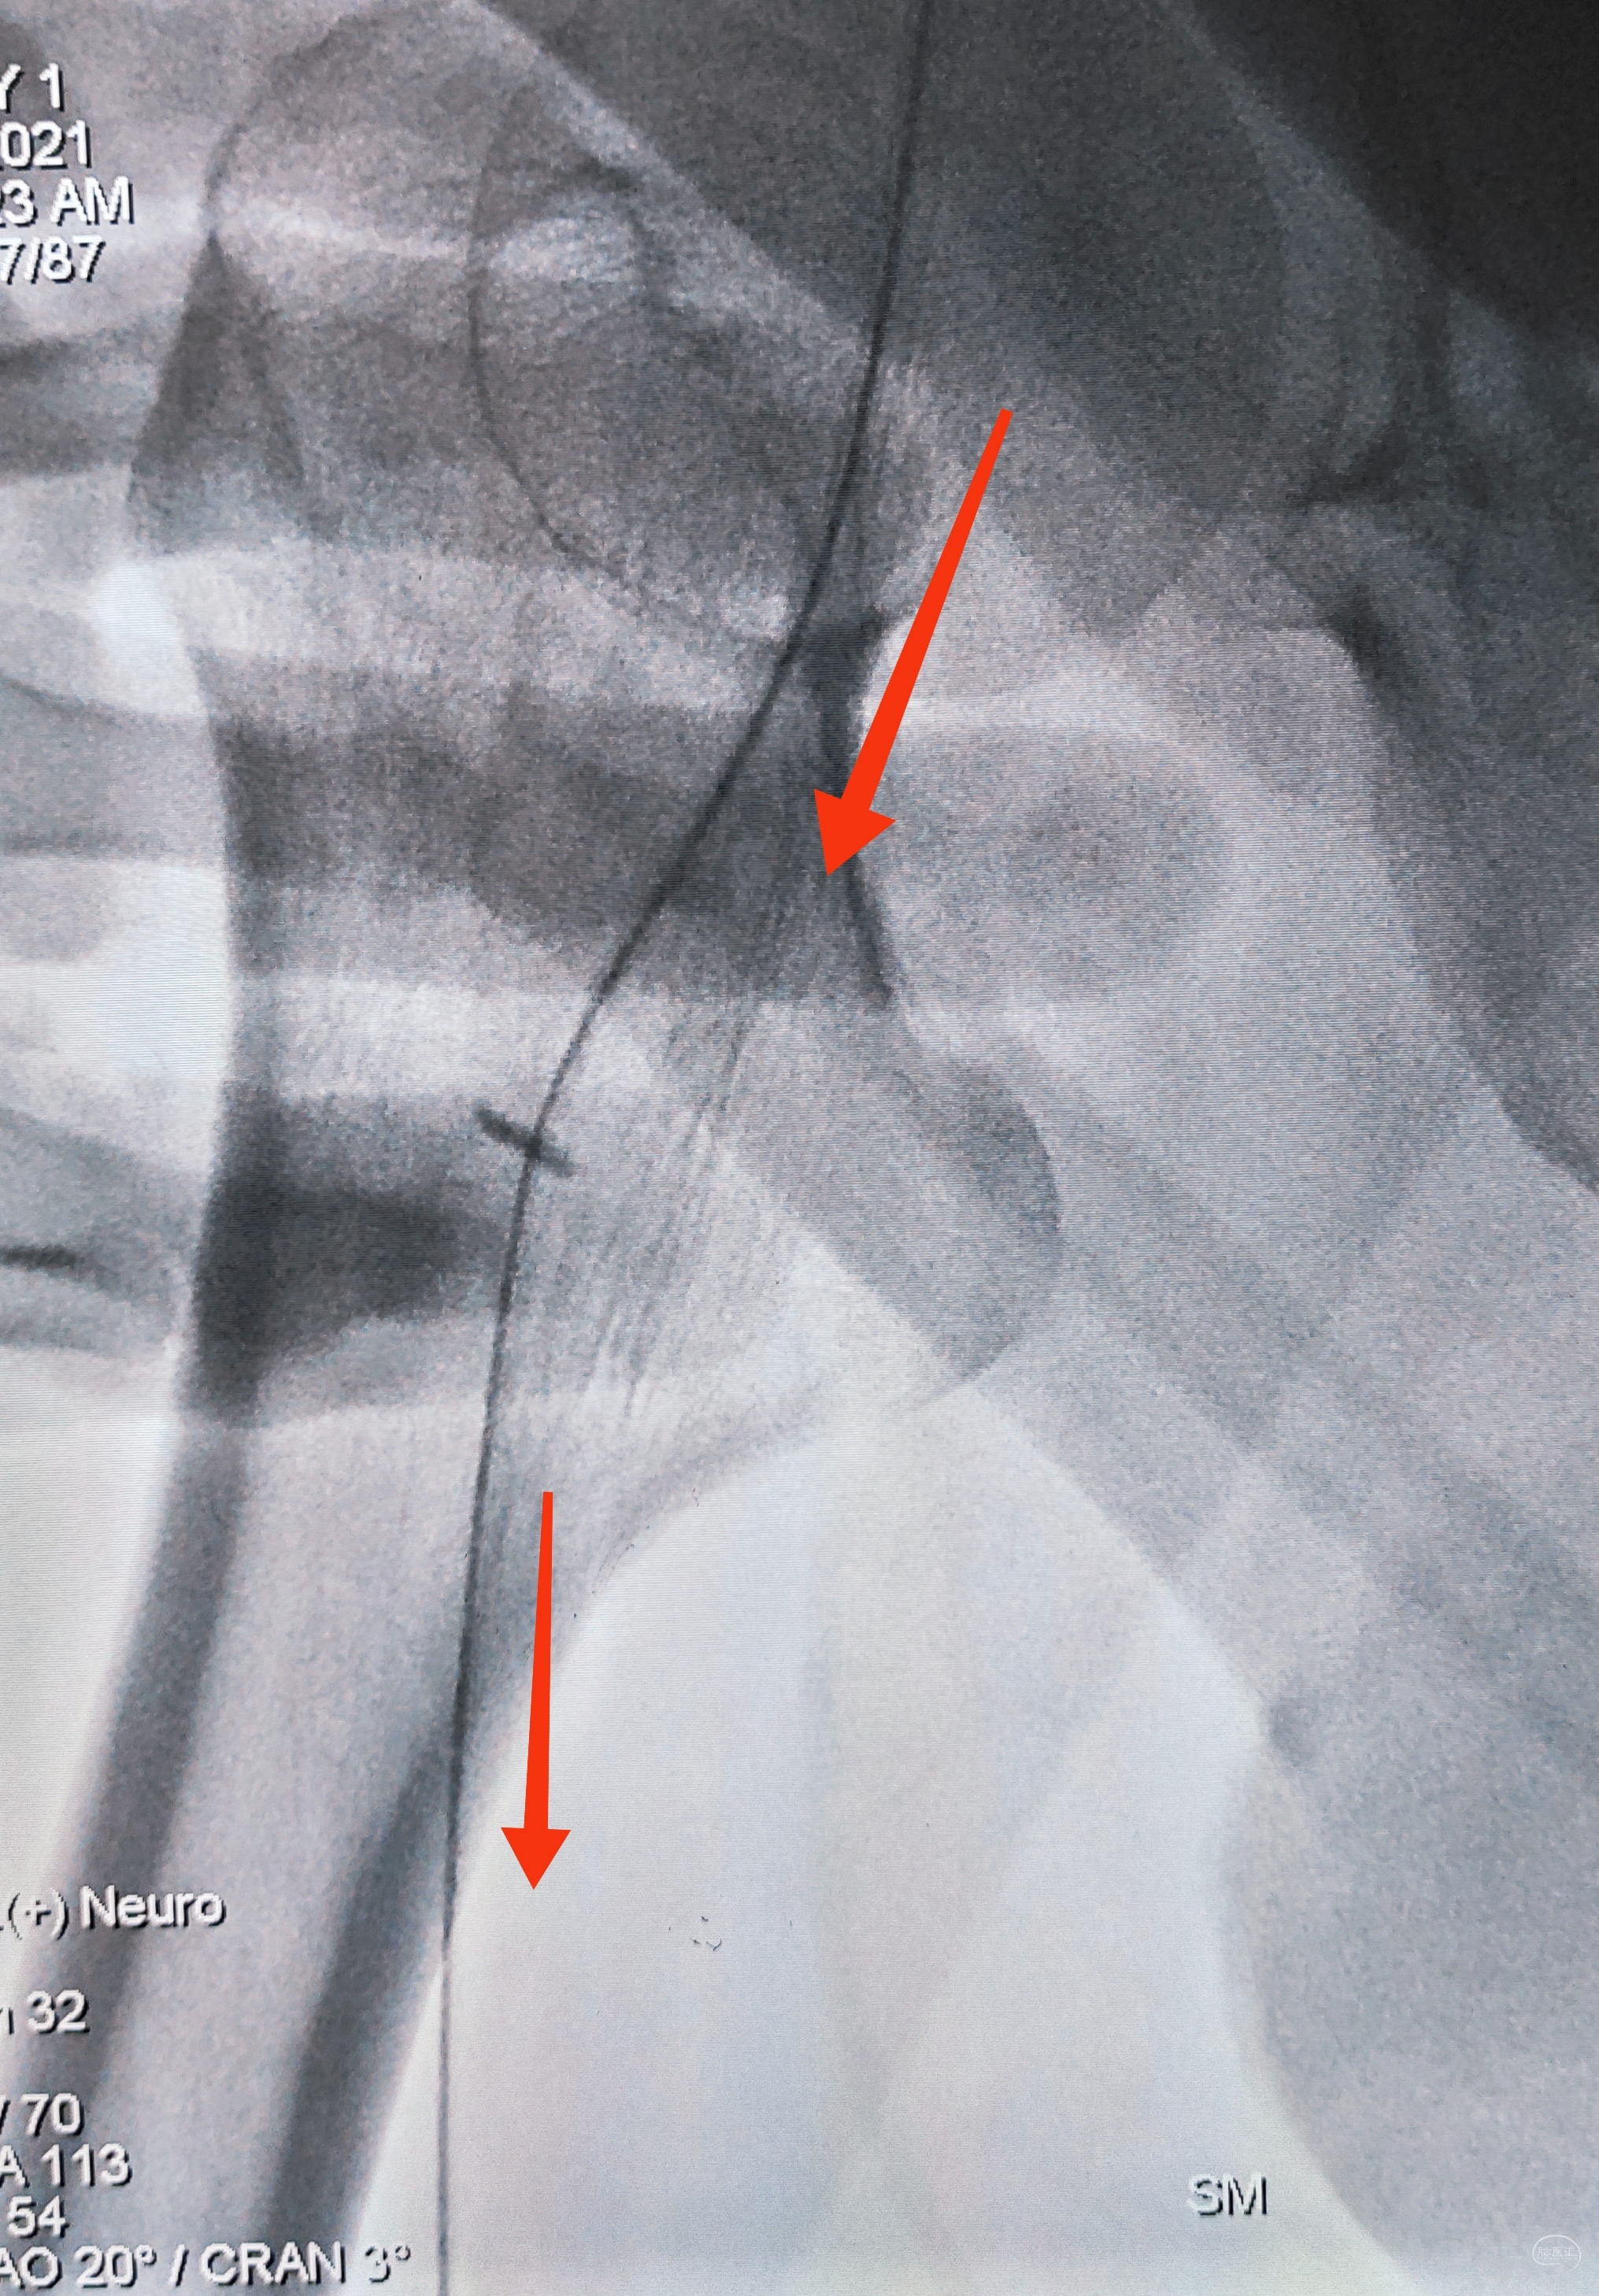

弓上造影初见:问题(一)左侧锁骨下动脉闭塞,主诉为头晕,双上肢收缩压差>20mmHg,这就是祸根?接着看弓上造影晚期像。

弓上造影晚期:剂量因素,逆流盗血隐隐可见,复合预期,那就看看对侧椎动脉情况吧